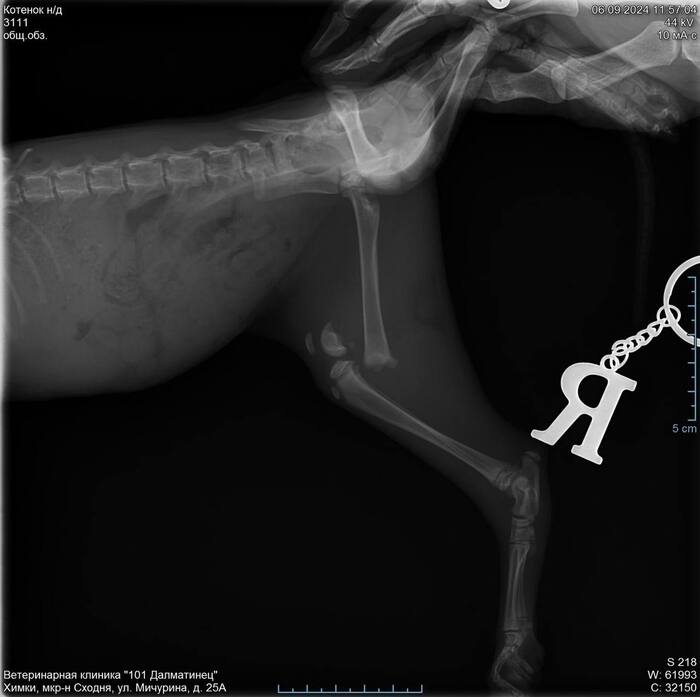

Вот в каком виде её нашли:

Далее у коти была операция с установкой спиц и последующем их извлечением, деньги на операцию собрали сотрудники ТЦ за пару часов.